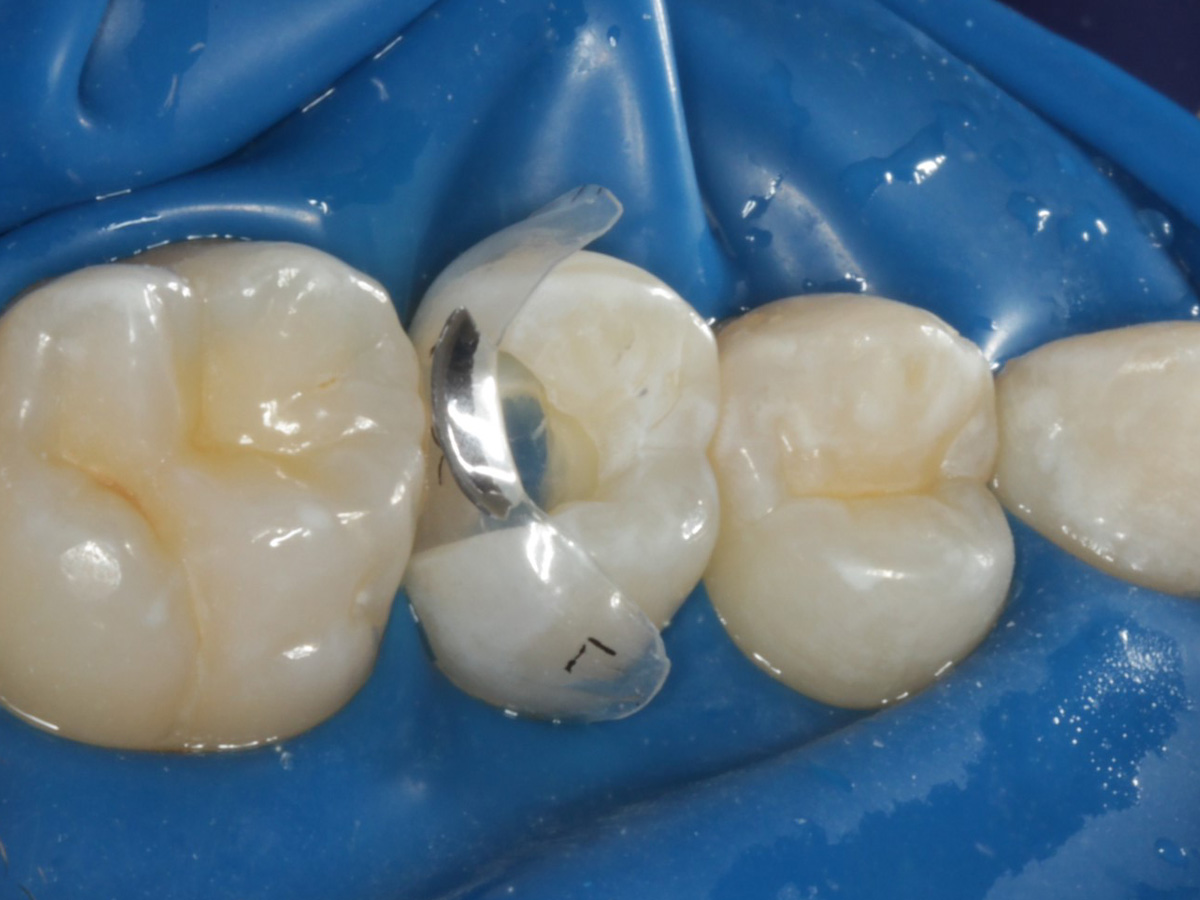

Abbildung 3

Quadrantenisolierung mit Kofferdam (x-heavy)

Abbildung 4

Schutz des Nachbarzahnes und des Kofferdams mit wiederverwandter Bioclear Biofit Matrize (gereinigt und sterilisiert)